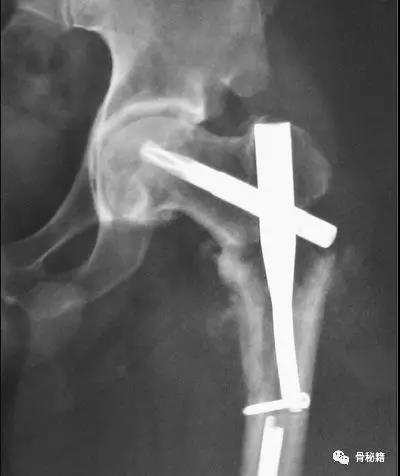

一个双膦酸盐治疗5年的患者粗隆下非典型骨折

采用了髓内钉固定,术后一年内固定失效